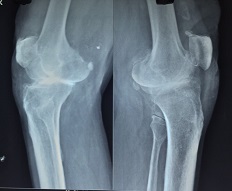

Tkr 69 Year Old

Tkr 73 Year Old